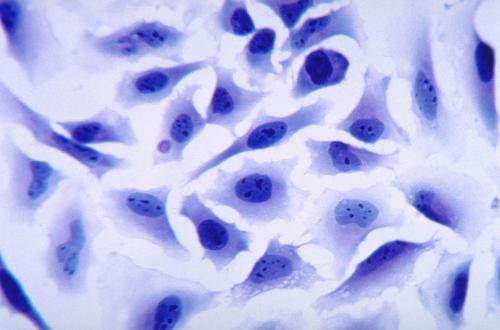

前言過繼性免疫治療是血液學的一種變革性治療方法,它通過基因工程在T細胞表達合成嵌合抗原受體(CAR)。針對 B 細胞白血病和淋巴瘤中的 CD19 抗原的 CAR-T 細胞已得到臨床認可,目前成為全球范圍癌癥中心實施的“常規” 治療手段。CAR結構由三部分組成:細胞外抗原識別結構域、跨膜結構域和含有CD3ζ或共刺激分子的細胞內信號轉導結構域。CAR-T細胞具有誘導體液和細胞免疫抗CAR應答的潛力,這